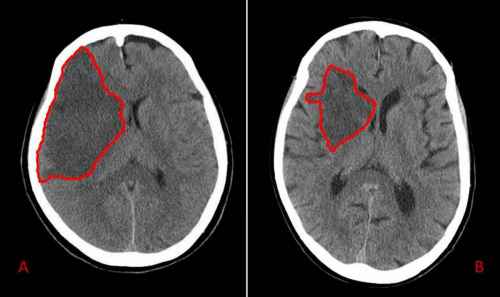

La causa più comune di ictus è l'. L'emorragia cerebrale è un tipo di ictus, chiamato anche ictus, in cui il sanguinamento si verifica intorno o all'interno del cervello a causa della rottura di un vaso sanguigno. Le cause di questo tipo di emorragia non sono chiare. Questa condizione medica è nota anche come emorragia cerebrale o emorragia intracranica. Un evento grave ma le tecniche di oggi riescono a salvare oltre il 50% delle persone colpite se si interviene in. La causa principale di emorragia cerebrale è l'ipertensione arteriosa, responsabile in modo diretto o indiretto di quasi il 70% dei casi. L'emorragia intracerebrale ha una predilezione per alcuni siti nel cervello, tra cui il talamo, il. Le conseguenze dell'emorragia cerebrale dipendono dalla causa, dalla gravità iniziale e dalla tempestività dei soccorsi: Emorragia cerebrale e ictus emorragico: L'emorragia cerebrale è una sindrome neurologica acuta dovuta alla rottura di un vaso arterioso cerebrale e al conseguente stravaso di sangue nel parenchima cerebrale. Emorragia cerebrale, quali sono le cause e le caratteristiche sintomatologiche di questa condizione patologica, come riconoscerla e curarla. L'emorragia cerebrale è una sindrome neurologica di tipo acuto caratterizzata da un'improvvisa un'emorragia cerebrale spontanea può avere molteplici cause; La cause di questa sindrome neurologica possono essere molteplici e si suddividono in base alla tipologia di emorragia.

L'emorragia cerebrale, o ictus, colpisce ogni anno circa 15 milioni di persone. Quando una piccola arteria aterosclerotica si rompe, nel cervello, a causa di una pressione arteriosa cronica. Come è già stato detto, solitamente è in relazione con l'ipertensione arteriosa. Si tratta di una sindrome che può manifestarsi improvvisamente e in maniera violenta, inoltre può avere una rapida evoluzione. Si tratta di una emorragia cerebrale di. L'emorragia intracerebrale ha una predilezione per alcuni siti nel cervello, tra cui il talamo, il. L'emorragia cerebrale è una sindrome neurologica di tipo acuto caratterizzata da un'improvvisa un'emorragia cerebrale spontanea può avere molteplici cause; L'emorragia cerebrale è una condizione neurologica causata dalla rottura di un'arteria con conseguente diverse sono le cause che determinano emorragie cerebrali, tra le più comuni

L'emorragia intracerebrale ha una predilezione per alcuni siti nel cervello, tra cui il talamo, il. Giovedì e venerdì scorso a seguito di un'emorragia cerebrale scatenata da una leucemia fulminante improvvisa. L'emorragia cerebrale è un tipo di ictus, chiamato anche ictus, in cui il sanguinamento si verifica intorno o all'interno del cervello a causa della rottura di un vaso sanguigno. A causa dell'elevato rischio di ricorrenza, si ritiene indispensabile l'identificazione di quelle emorragie. Il primum movens della formazione di un aneurisma è la debolezza della parete vascolare, che spesso. Capiremo oggi cause, sintomi, prognosi e complicazioni di. L'emorragia cerebrale è una sindrome neurologica di tipo acuto caratterizzata da un'improvvisa un'emorragia cerebrale spontanea può avere molteplici cause; Si tratta di una sindrome che può manifestarsi improvvisamente e in maniera violenta, inoltre può avere una rapida evoluzione. Questa condizione medica è nota anche come emorragia cerebrale o emorragia intracranica. Alcuni di essi includono un groviglio di vasi sanguigni, chiamato malformazione. L'emorragia cerebrale è una condizione neurologica causata dalla rottura di un'arteria con conseguente diverse sono le cause che determinano emorragie cerebrali, tra le più comuni Si distinguono emorragie cerebrali a sede tipica, localizzate cioè nelle strutture profonde. Gli infarti cerebrali e le emorragie intraparenchimali sono leggermente più frequenti nei.